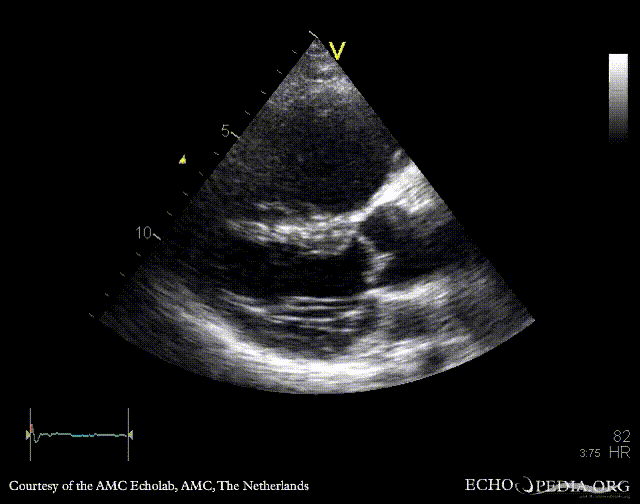

E00346.gif E00347.gif

PLAX: enlarged right ventricle in patient with carcinoid PSAX: enlarged right ventricle in patient with carcinoid, diastolic flattening of IAS